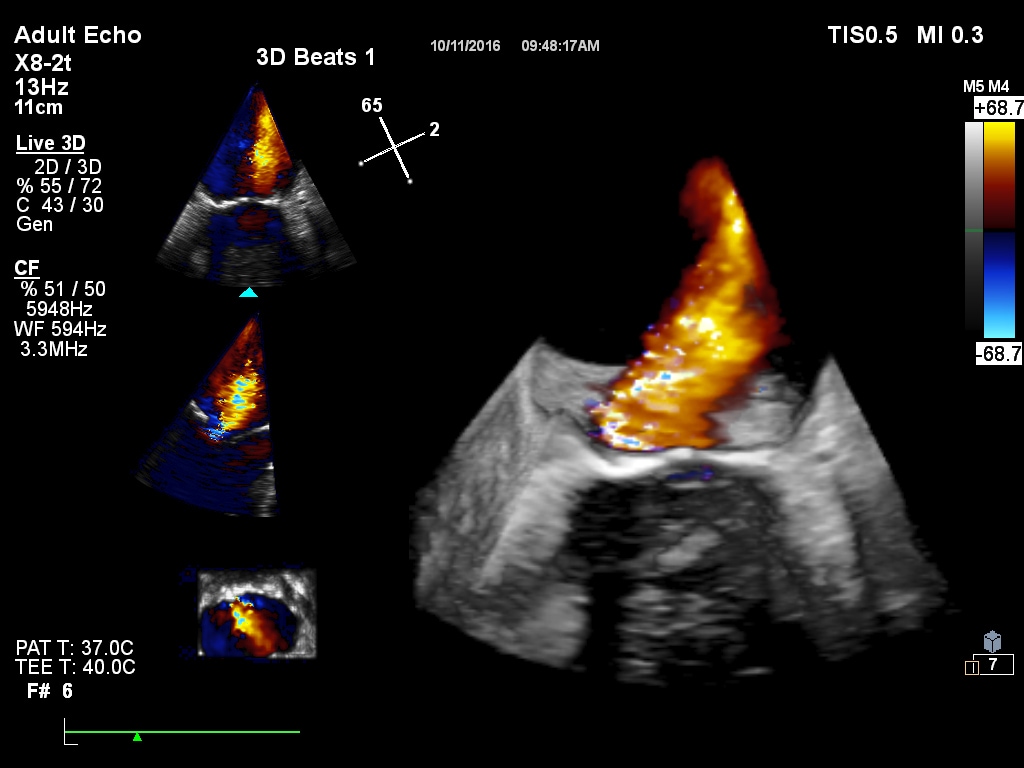

New cardiovascular capabilities

X8-2tトランスデューサ

次世代のLive 3D TEEがここにあります。音響設計が改善されており、EPIQ nSIGHTイメージング技術で最適に機能するようになっています。